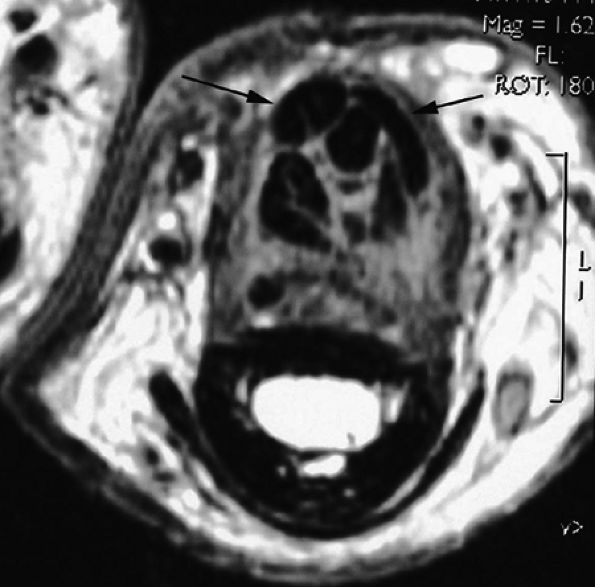

seen with synovial sarcomas. Bone and joint invasion is possible.168 Ultrasonography shows a nonspecific solid mass with a variable color Doppler signal. MR images are specific, depicting a well-defined mass with hemosiderin deposits. Typical signal void artifacts are seen on all sequences, particularly on gradient-echo images, and a more heterogeneous and predominantly low signal is found on T2-weighted images.162,166,169 The lesion typically enhances after intravenous injection of gadolinium (Fig. 11.74). The tendon sheath of the flexor digitorum tendons is usually partially or totally enveloped; the extensor tendons are less commonly involved. Some lesions may be more aggressive, and diffuse lesions are seen in multiple locations with invasion of both the flexor and extensor tendons (Fig. 11.75).170